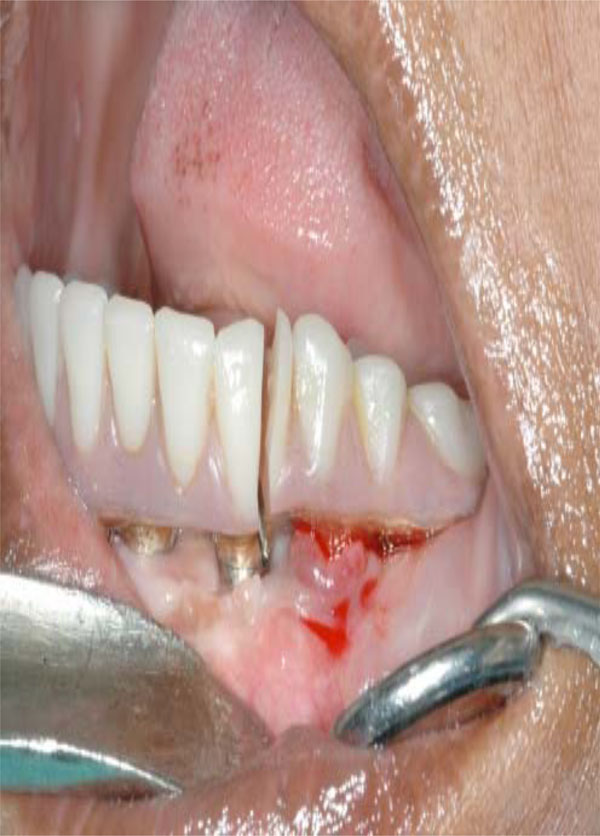

Esthetic demands tend to be more dramatic with maxillary prostheses than mandibular prostheses (Fig. 3). As per Zarb and Schmitt, unlike mandibular implant prostheses were hygienic type designs have proven to be functionally and esthetically acceptable, maxillary implant prostheses demand different sized and shaped labial/buccal flanges that may or may not compensate for optimal esthetics, phonetics, and masticatory function (Fig. 4). Additionally prosthetic gingival tissues are often required due to resorptive patterns of edentulous maxillae. Resorptive patterns in maxillae are dissimilar to mandibular resorption pattern: maxillae resorb superiorly, posteriorly, and medially: mandible resorbs inferiorly, anteriorly, and laterally [26, 27].

Excellent maintenance and oral hygiene after 3 years from maxillary hybrid prosthesis delivery.